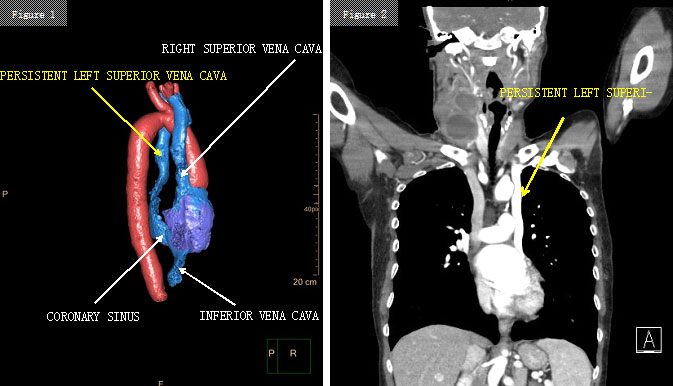

92% der persistierenden linken Vena cava superiorer (PLSVC) fließen in den Sinus coronarius (Abb. 1 und 2).